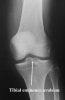

영상 검사

X-ray에서는 간혹 segond fracture나 deep sulcus sign이 보이는 경우 진단에 추가적인 도움을 줄수 있으나 빈도가 흔하지 않거나 발견하기가 쉽지 않습니다.

X-ray : Tibial eminence avulsion fx